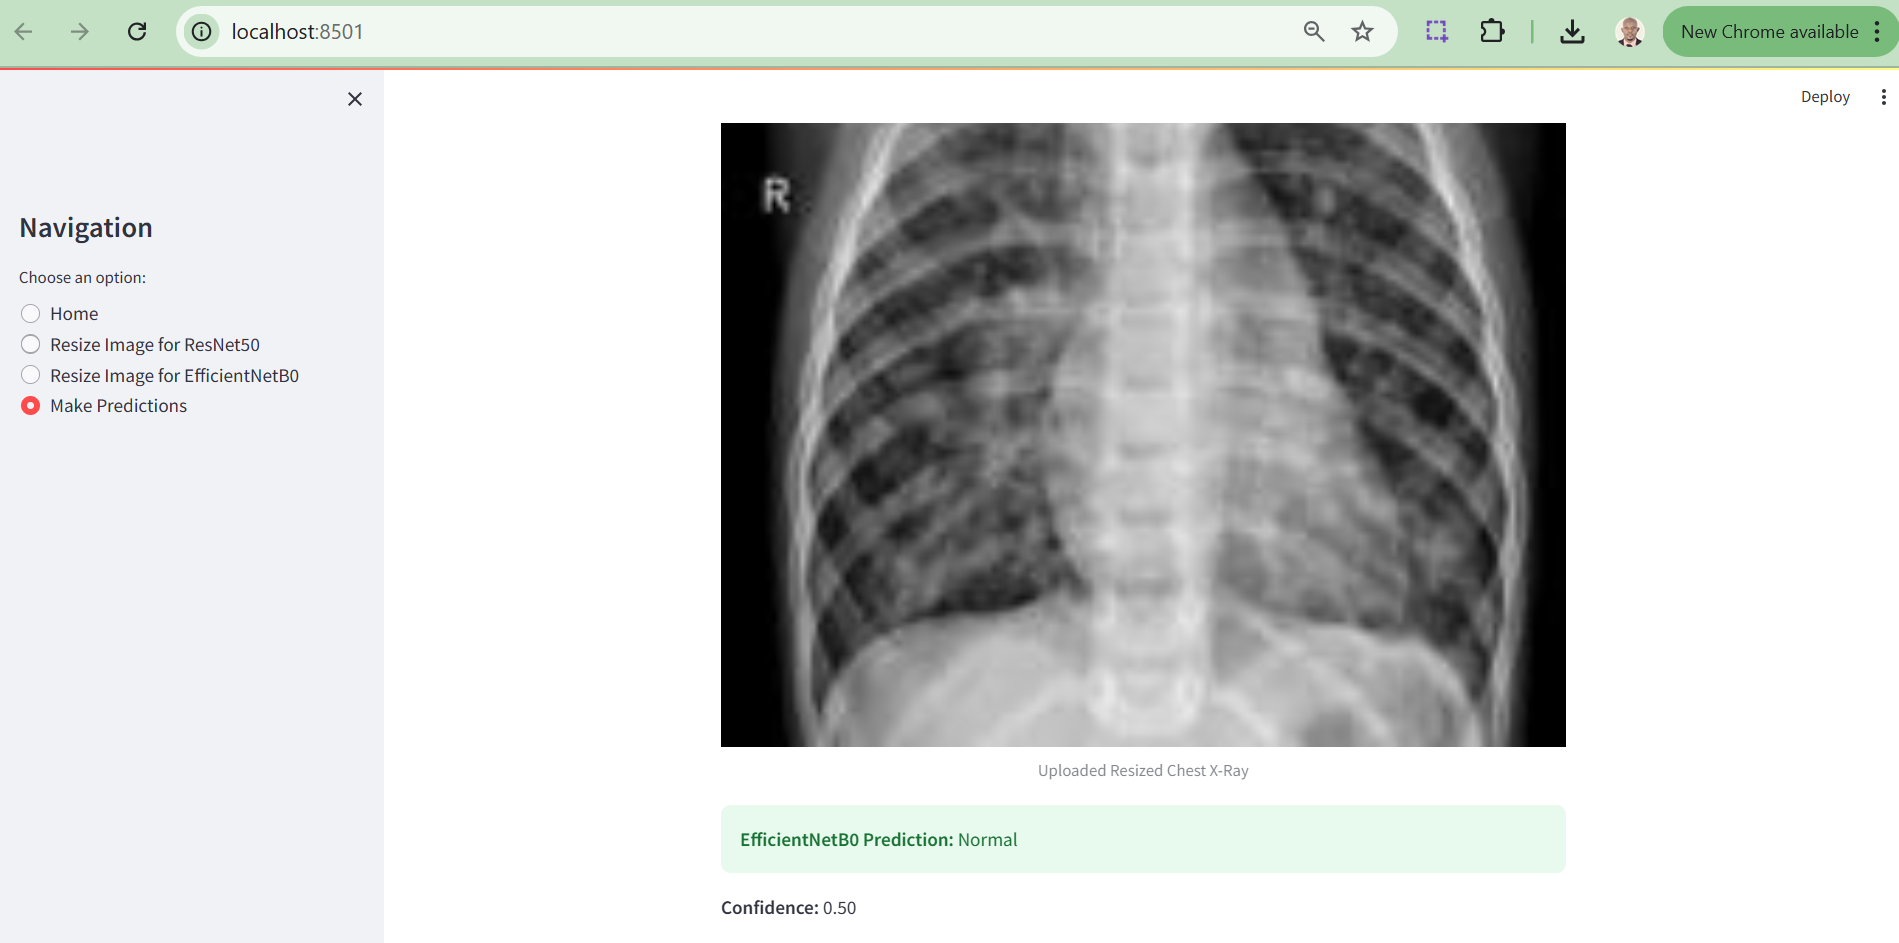

As part of this research, a web-based tool was developed to enable clinicians and researchers to easily utilize the trained deep learning models, ResNet50 and EfficientNetB0, for pneumonia detection. This application bridges the gap between advanced computational techniques and clinical usability by providing an interactive and user-friendly interface.

i. Resize Chest X-Ray Images: Resize images to the required dimensions for each model (ResNet50: 224x224 pixels, EfficientNetB0: 150x150 pixels) using the "Resize Image" options in the sidebar.

ii. Upload and Analyze X-Ray Images: After resizing, users can upload the processed image and receive diagnostic predictions with associated confidence scores.

iii. Visualize Results: Users can compare the predictions of both models side-by-side, enabling insights into their performance and clinical applicability.

Below are screenshots of the tool interface:

Figure 9. Prediction Output Section

The results of this study reveal the strengths and limitations of leveraging deep learning models, EfficientNetB0 and ResNet50, for pneumonia detection. EfficientNetB0 demonstrated consistent performance when tested with properly resized images, highlighting its robust design for transfer learning and medical imaging tasks. However, its reliance on exact input dimensions underscores a limitation for real-world applications, where data may not always conform to predefined standards. ResNet50, on the other hand, showcased potential but suffered from implementation errors during prediction, a hiccup reflective of the constraints of research timelines rather than its architectural capability.

Further notable limitation of this research’s web implementation is that the EfficientNetB0 model successfully generates prediction results only when users upload pre-optimized X-ray images, whereas the ResNet50 model currently fails to produce predictions due to an unresolved error. While significant efforts were made to address this issue, time constraints prevented its resolution within the scope of this research. This limitation will be prioritized and rectified in subsequent phases of the study to ensure a fully functional diagnostic tool.